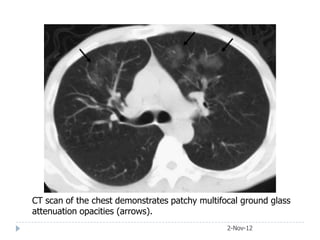

CT scan of the chest demonstrates patchy multifocal ground glass

attenuation opacities (arrows).

Case 4 • Male, 60, admitted to hospital with 2-wk H/O myalgia, headache, dyspnoea and cough without sputum. • O/E severely ill, cyanosed and delirious with T:39°C; P:110/min, RR:40/min and BP:110/60mmHg. PO2:43mmHg, PCO2:37mmHg, TLC 4600/cumm and urea 4 mmol/L. • He had received amoxicillin for 6 days before admission without improvement. CXR shows extensive bilateral multilobar consolidation. He kept birds as a hobby and one of his budgerigars 2-Nov-12

The clinical diagnosis of psittacosis was subsequently confirmed by serology tests. He was treated with intravenous fluids, oxygen and tetracycline and recovered fully 2-Nov-12

CT scan ofthe chest demonstrates patchy multifocal ground glass attenuation opacities (arrows). 2-Nov-12